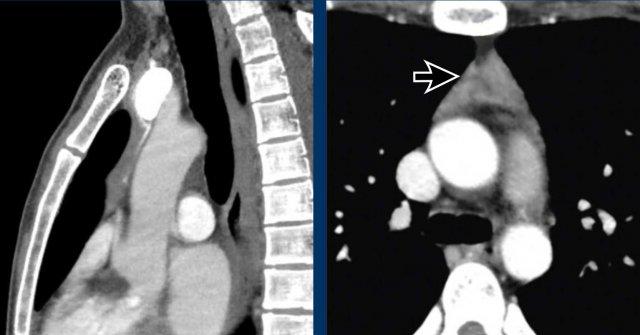

Các hình ảnh này của một nam giới 71 tuổi.

Trên CT ngực, tình cờ phát hiện một khối ở tuyến ức.

Hãy phân tích các hình ảnh. Nhận định của bạn là gì?

Hình ảnh

Một phần tổn thương có ngấm thuốc cản quang và có một số vôi hóa, có thể nằm ở thành nang.

Khi một tổn thương tuyến ức có thành phần đặc, nguyên tắc là… “khi còn nghi ngờ, hãy phẫu thuật cắt bỏ”.

Tổn thương đã được phẫu thuật cắt bỏ dựa trên kết quả CT và kết quả giải phẫu bệnh cho thấy đây là u tuyến ức dạng nang.